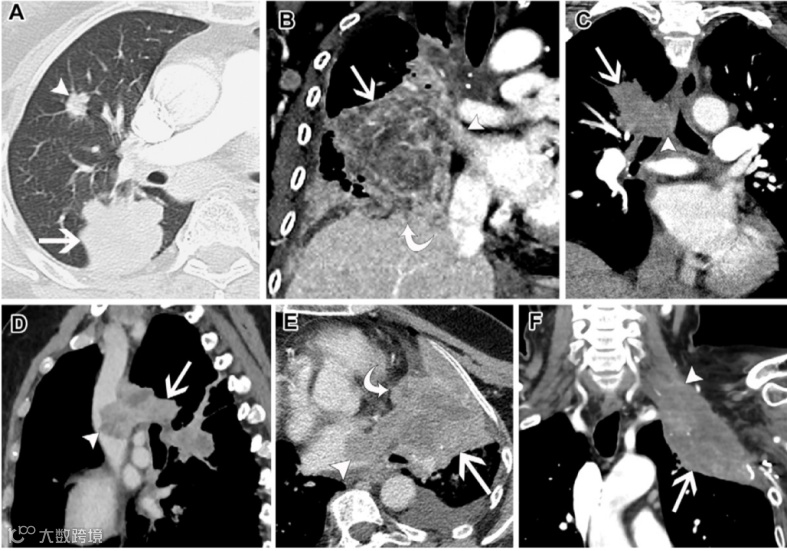

图4. 六例T4期肺癌患者。

(A)77岁女性非小细胞肺癌(NSCLC)患者的轴位非增强胸部CT图像(肺窗),显示右下叶肿块(箭头),并伴有右中叶的独立肿块结节(短箭头)。

(B)57岁女性NSCLC患者的冠状增强胸部CT图像(软组织窗),显示右肺的大型中央肿块(直箭头),侵犯纵隔(短箭头)和右膈肌(弯箭头)。

(C)73岁女性NSCLC患者的冠状重建增强胸部CT图像(软组织窗),显示右上叶肺肿块(箭头),侵犯气管远端和气管分叉(短箭头)。

(D)60岁女性NSCLC患者的矢状重建增强胸部CT图像(软组织窗),显示右上叶和右下叶均受累的肿块(箭头),并突入上腔静脉(短箭头)。

(E)64岁女性NSCLC患者的轴位增强胸部CT图像(软组织窗),显示左下叶肺癌(直箭头),侵犯心包和心外膜脂肪(弯箭头),并涉及左心房(短箭头)。

(F)63岁女性NSCLC患者的冠状重建增强胸部CT图像(软组织窗),显示左上叶上纵隔肿瘤(箭头),侵犯C8水平以上的左臂丛神经(短箭头)。